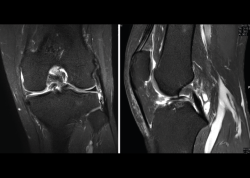

Figura 35. Corte de secuencia coronal y sagital de resonancia magnética de rodilla: rotura en asa de cubo del menisco interno con fragmento desplazado al intercóndilo.

1.2. Ligamentos

Se visualizan como estructuras lineales hipointensas en todas las secuencias.